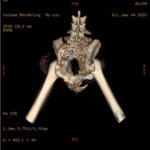

Gracias a vosotros por fin hemos podido realizar el TAC que necesitaba Allan. Os dejamos por aquí algunas de las imágenes y el primer informe emitido por el hospital.

Allan sigue ingresado y tendrá que estarlo varios días más, no sabemos aún cuántos. Deben estabilizarlo y observarlo antes de valorar si es conveniente operarlo. El estado del tórax sigue siendo delicado y tienen que controlar el encharcamiento que tiene en un pulmón. El TAC ha mostrado, además de nuevas fracturas, fracturas anteriores. Es decir, Allan no sólo está así porque recientemente haya recibido un golpe, sino que tiene signos de haber recibido al menos otro golpe anteriormente que también le produjo fracturas, unas fracturas que “se han soldado como han podido”. Como no tenemos ninguna información de Allan hasta la pasada semana que fue cuando recibimos el aviso, no sabemos si antes era capaz de caminar o de hacer caca él solito.